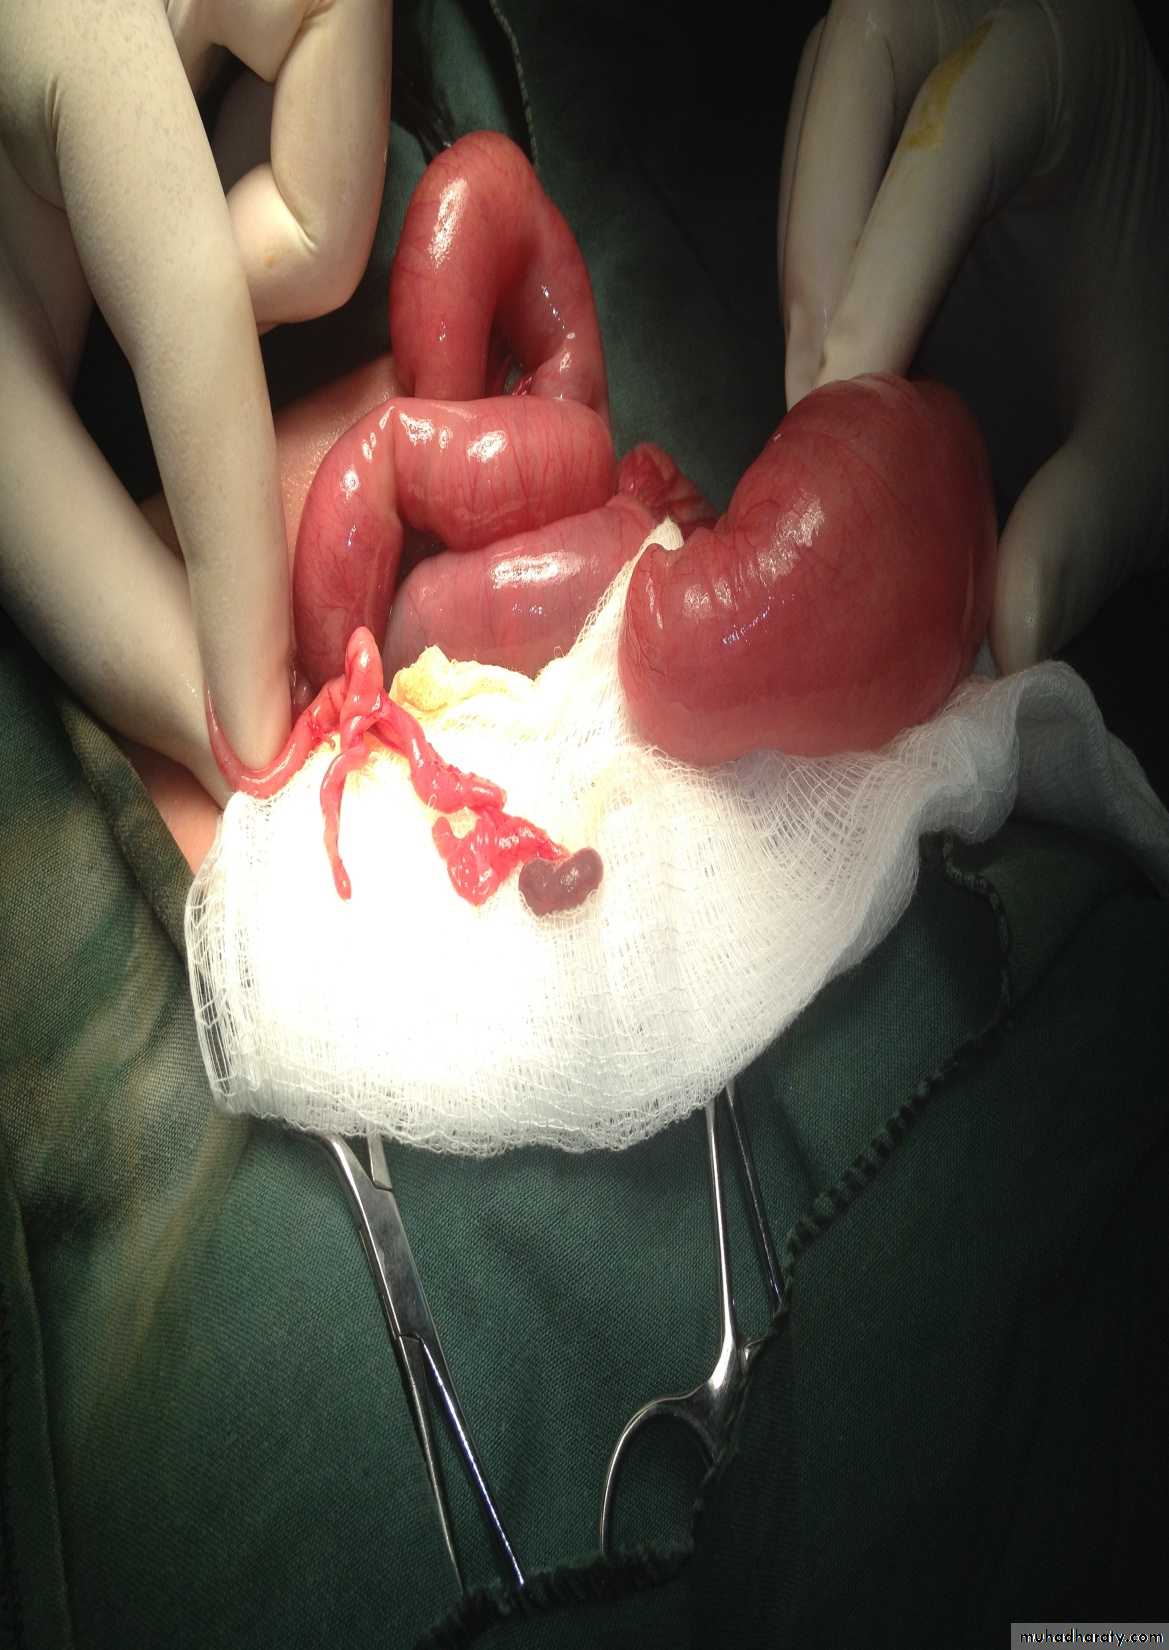

Surgery called pull-throughAbdominal Wall Defects

Diagnosis: omphalocele

Description:• Huge dilatation

• Central umbilicus

• Liver present

Treatment:

It is no emergency condition• Cover

• Incubation

• Give fluid

• Use silo bag